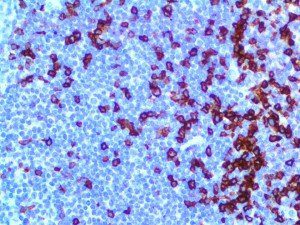

The first cytokines released are interleukin 1β (IL-1β) and tumor necrosis factor-α (TNF-α), which attract a variety of circulating white blood cells (WBCs) to the infection site, including neutrophils, monocytes, macrophages, and natural killer (NK) cells. This response, along with the antipathogenic chemicals released by these cells (i.e., complement), comprise the innate immune response. These cells directly attack the invading pathogen and also release additional cytokines, chief among them interleukin-1 and 6 (IL-6). IL-6 is essential for invoking the adaptive immune response, which calls T-cells, B-cells, and T helper (Th) cells to the infection site. IL-6 also stimulates further recruitment, proliferation and activation of macrophages.

It is the ICU physician who is most likely to witness one of the deadliest manifestations of the abnormal immunological response, the cytokine storm syndrome (CSS). This response is also referred to by some as the cytokine release syndrome (CRS). CSS is characterized by continuous activation and expansion of macrophage and lymphocyte populations, which secrete large amounts of cytokines, causing the cytokine storm. This massive cytokine release is akin to hemophagocytic lymphohistiocytosis (HLH) disease, a syndrome characterized by initial unchecked and persistent activation of cytotoxic T lymphocytes and NK cells.

Clinical and laboratory manifestations of HLH include fever, enlarged liver and/or spleen, neurologic dysfunction, coagulopathy, liver dysfunction, cytopenias (i.e., low levels of erythrocytes, leukocytes, and/or platelets), hypertriglyceridemia, hyperferritinemia, hemophagocytosis, and eventually diminished NK cell activity as the immune system becomes progressively paralyzed. HLH can be familial (primary HLH) or secondary to another disease process (sHLH), such as rheumatic disease, in which it is referred to as macrophage activation syndrome (MAS, characterized by elevated ferritin).